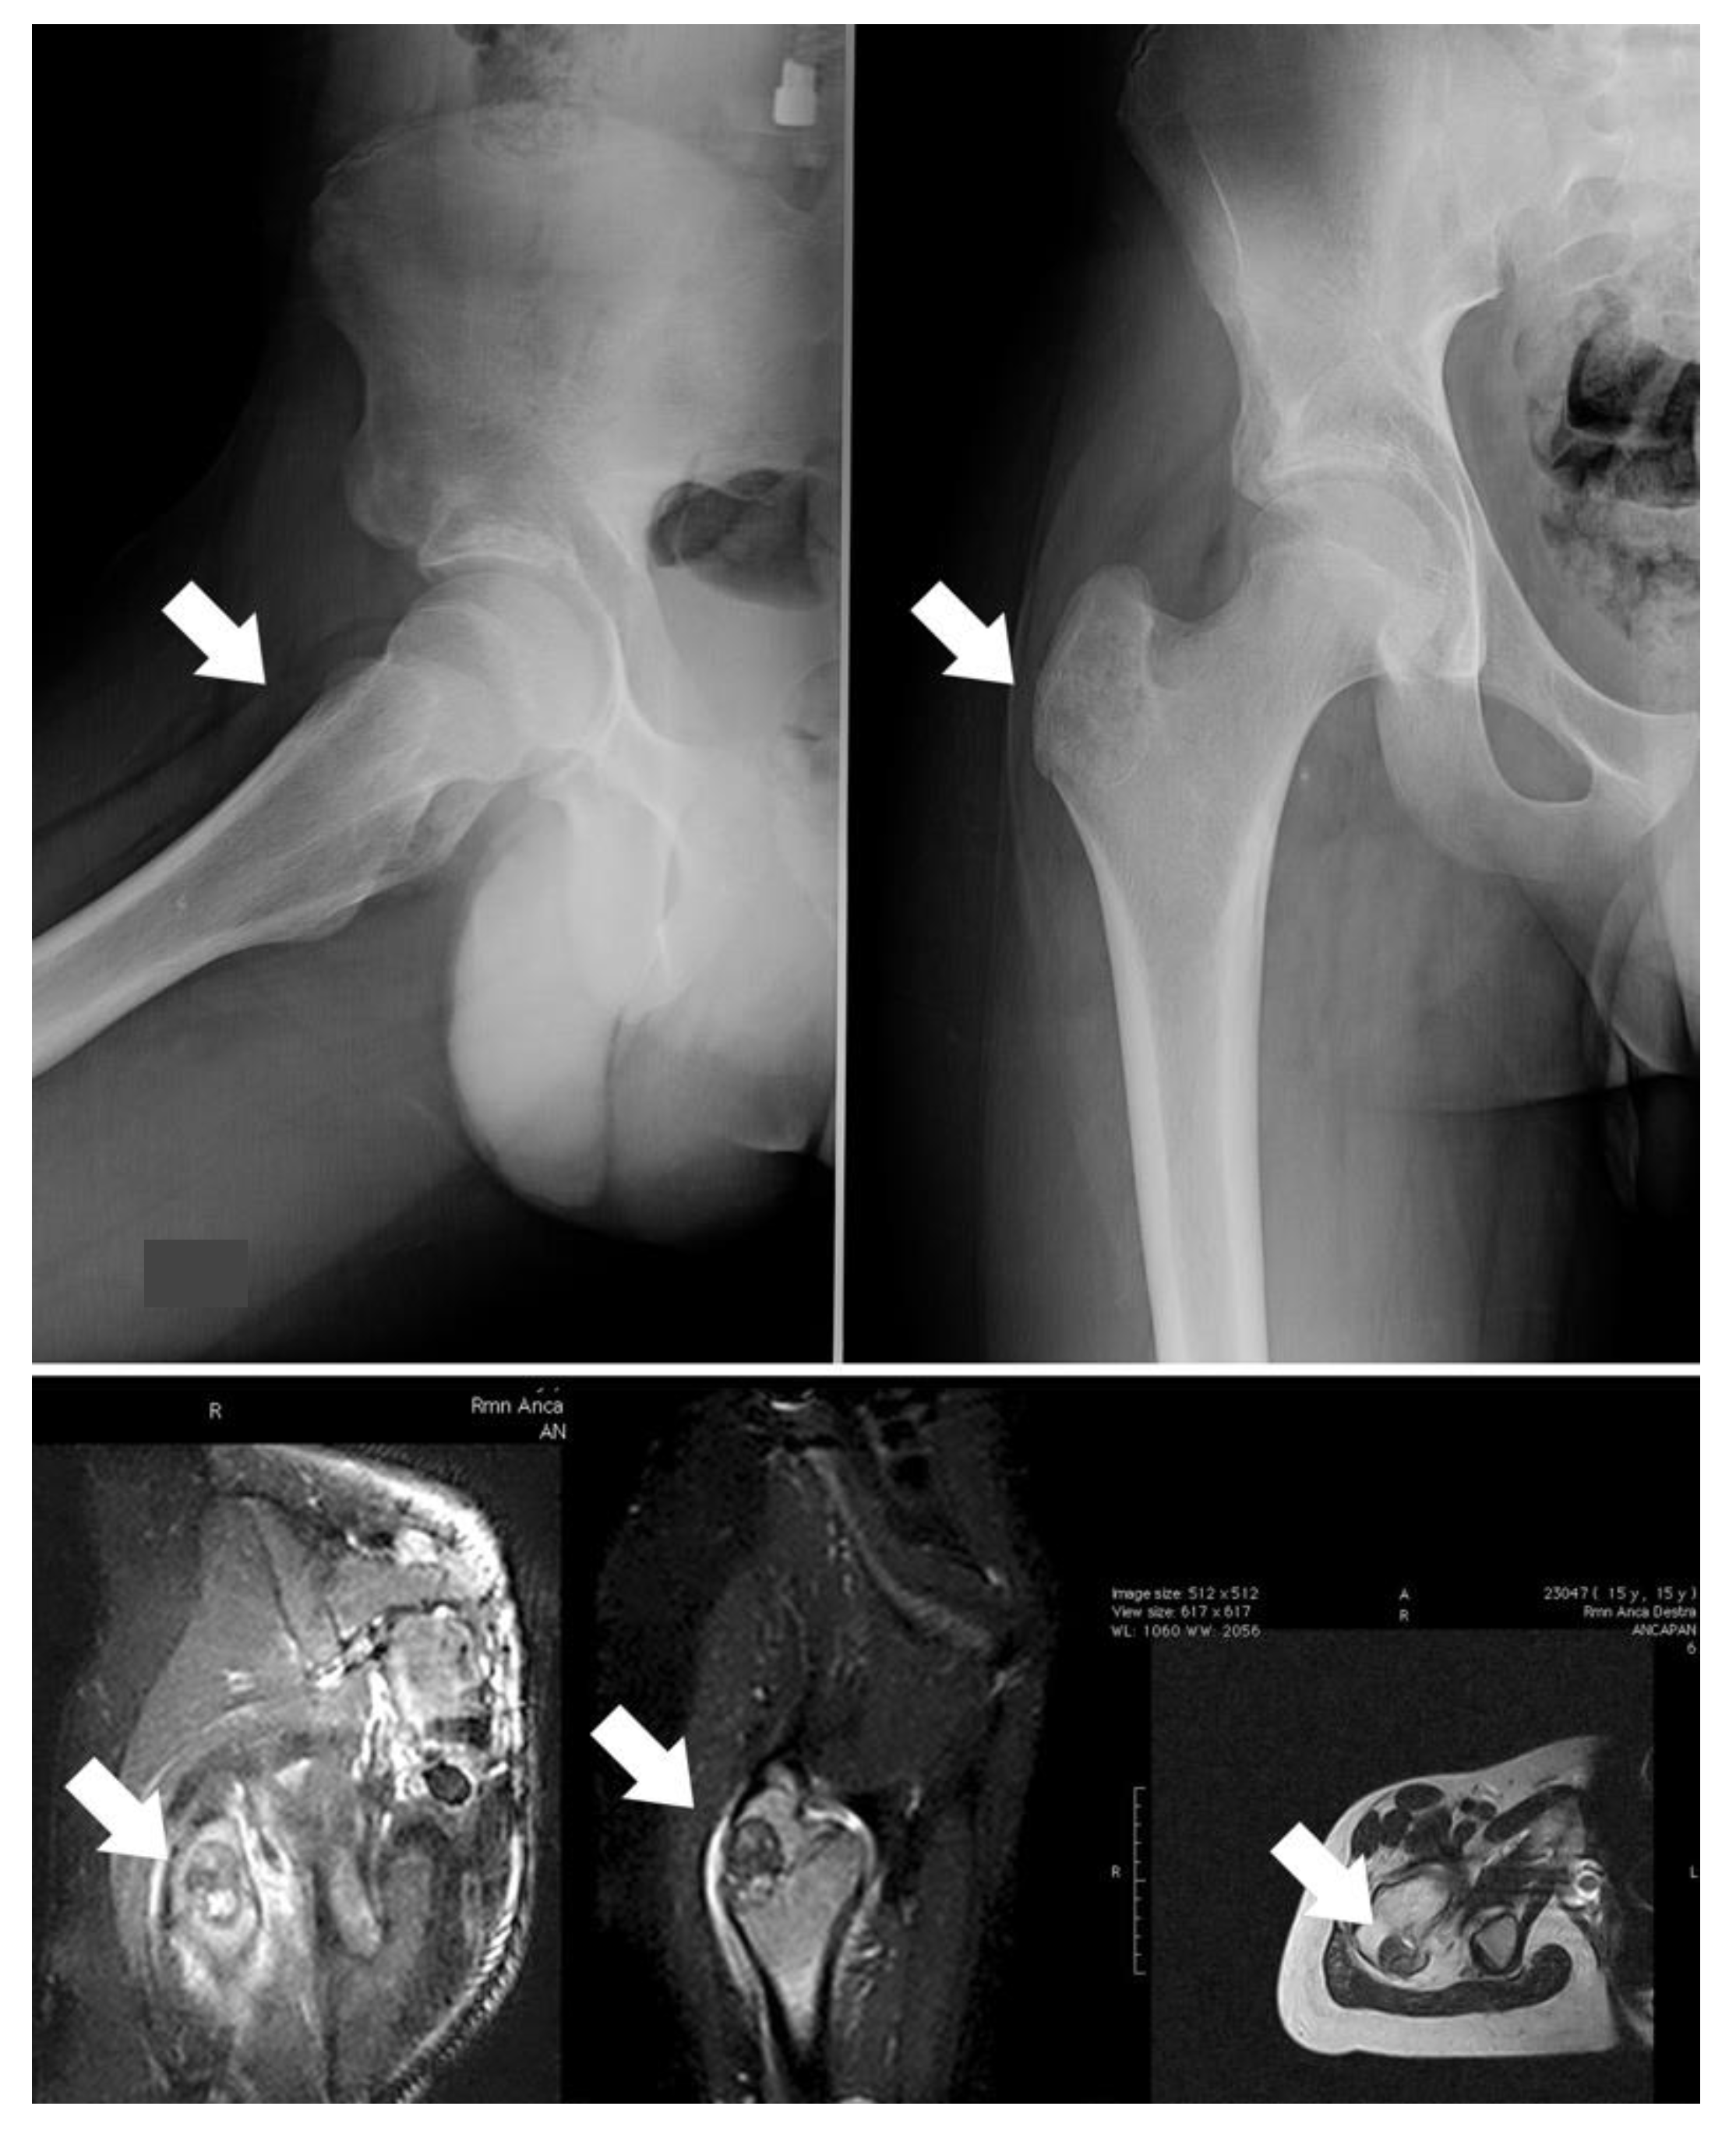

In the presented series, a proximity to nerves was the main indication for surgery; indeed, thermoablation can cause them damage. Additionally, tumor size and shape have to be considered: an irregular shape can be a contraindication for minimally invasive treatment, such as a risk of fracture. In case 3, we preferred to surgically remove the tumor and then to fill the cavity with a homograft to decrease the risk of great trochanter avulsion (Figure 2). Localization should also be considered in the indications for surgery.

When OBLs are located in the limbs, an intralesional approach can be considered the best-choice treatment, although, if the lesion is small, thermoablation has to be carefully assessed. Surgery is necessary in cases with a risk of fracture (case 3; Figure 4) because bone filling is required. Resection can also be considered for OBLs located near neurovascular bundles.

Figure 4. Case 3, a male patient with OBL of the right trochanter; on the upper image, the X-ray shows a quite well-defined osteolytic lesion (white arrows); on the lower image, the related MRI highlights the important oedema surrounding the OBL. The indication for surgery was based on the risk of a fracture due to both eventual RF thermoablation and the action of pelvic-trochanteric muscles.